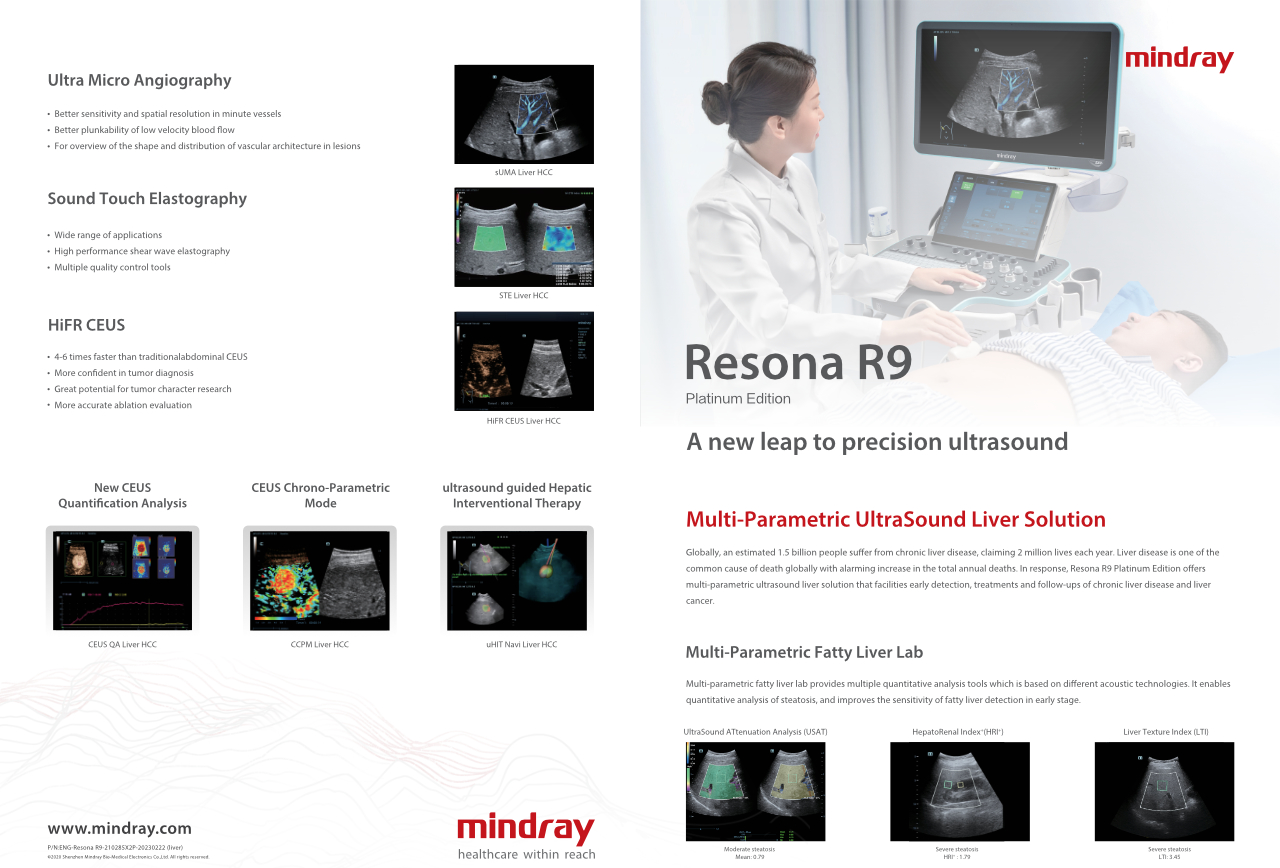

?QuĂ© tan claramente se puede ver un hĂgado?

Para las lesiones hepĂĄticas focales, como el hemangioma o el cĂĄncer de hĂgado, el diagnĂłstico por imĂĄgenes mediante ecografĂa con contraste cumple un papel importante. La tecnologĂa de diagnĂłstico por imĂĄgenes con contraste UWN+ (no lineal ultraancha) puede ayudar a obtener una mejor penetraciĂłn, una mayor relaciĂłn contraste-tejido, con un IM mĂĄs bajo y una observaciĂłn del tiempo de perfusiĂłn mĂĄs prolongada.